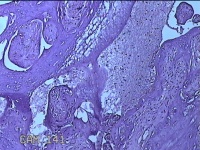

胎盘组织

性别

女

年龄

30岁

临床诊断

妊娠合并中度贫血

一般病史

停经39+2周,B超检查发现羊水偏少6小时。

标本名称

大体所见

灰白暗红色胎盘组织16.5x14.5x3.5㎝一个,表面光滑,血管突出,颜色发暗,绒毛面结节状,有轻度糜烂,暗红色,有少许凝血块,切面见绒毛内有暗红色血液渗出,边缘蜕膜可见多个小血肿,脐带39x1.8x0.3㎝,螺旋状扭曲,切断脐带,见脐血管内有凝血块。